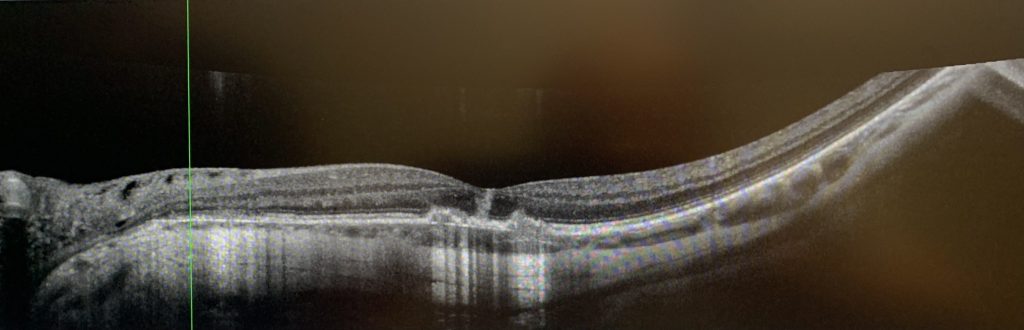

The day after the treatment, my symptoms continued to worsen, with my left eye’s vision becoming increasingly blurred and a shadow appearing in the upper left portion of my visual field. Although the Amsler grid test did not reveal any distortion, the black dot in the center of the grid would disappear when I moved my eye. During a follow-up examination at the clinic, my left eye’s vision had deteriorated further to 20/50. After reviewing the latest results from various specialized ocular tests and consulting with three retinal specialists in the clinic, I was ultimately diagnosed with uveitis.

After a comprehensive evaluation, Dr. Freund diagnosed my eye condition as punctate inner choroiditis, a rare form of multifocal chorioretinal inflammatory disease that can result in choroidal neovascularization. In light of my prior severe macular degeneration, this condition may significantly jeopardize my visual prognosis. Given the rapid progression of the condition, immediate treatment was necessary. Dr. Freund promptly prescribed an emergency medication plan and arranged for relevant laboratory tests, while also inviting a rheumatologist to participate in the consultation and join the treatment team